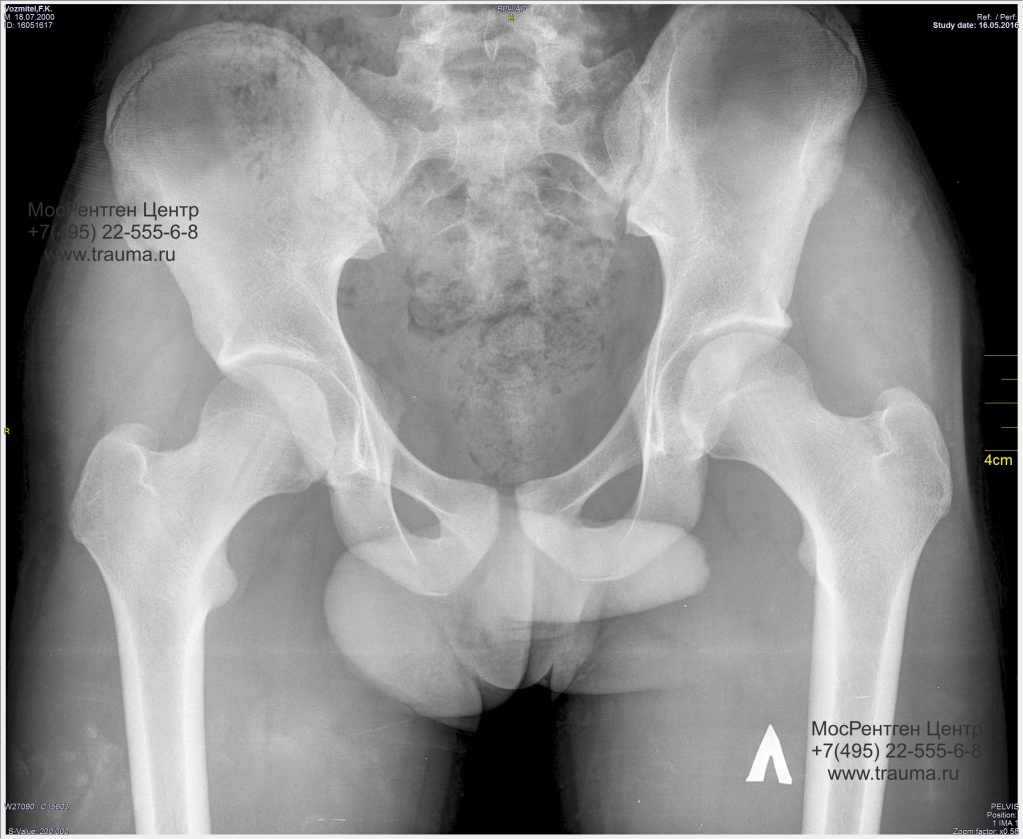

Рентген ТБС: Нормальные показатели